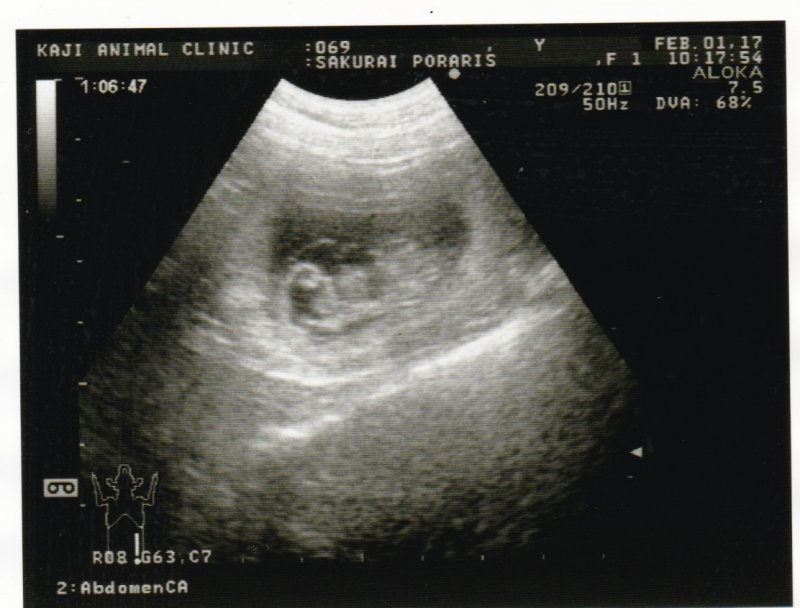

本日2017年2月1日に妊娠鑑定の結果、ポラリスの妊娠が確認できました。出産予定は、3月3日前後ごろになりそうです。母子ともに元気な子犬が産まれるように母犬ポラリスとスタッフと共に頑張ります。これからポラリスが出産するまでホームページやブログでご紹介させていただきますので、ご覧ください。

妊娠鑑定で、7頭の子犬が確認できました。